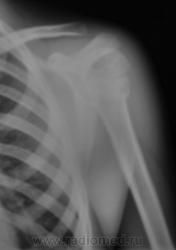

Но у первого пострадавшего помимо перелома и вывиха в плечевом ещё и надрыв/разрыв ключично-акромиального сочленения.

На мой взгляд, вывих спорный.

В обоих случаях перелом хирургической шейки плечевой кости. А почему только в одной проекции? Мы всегда снимаем в двух - в прямой и аксиальной.